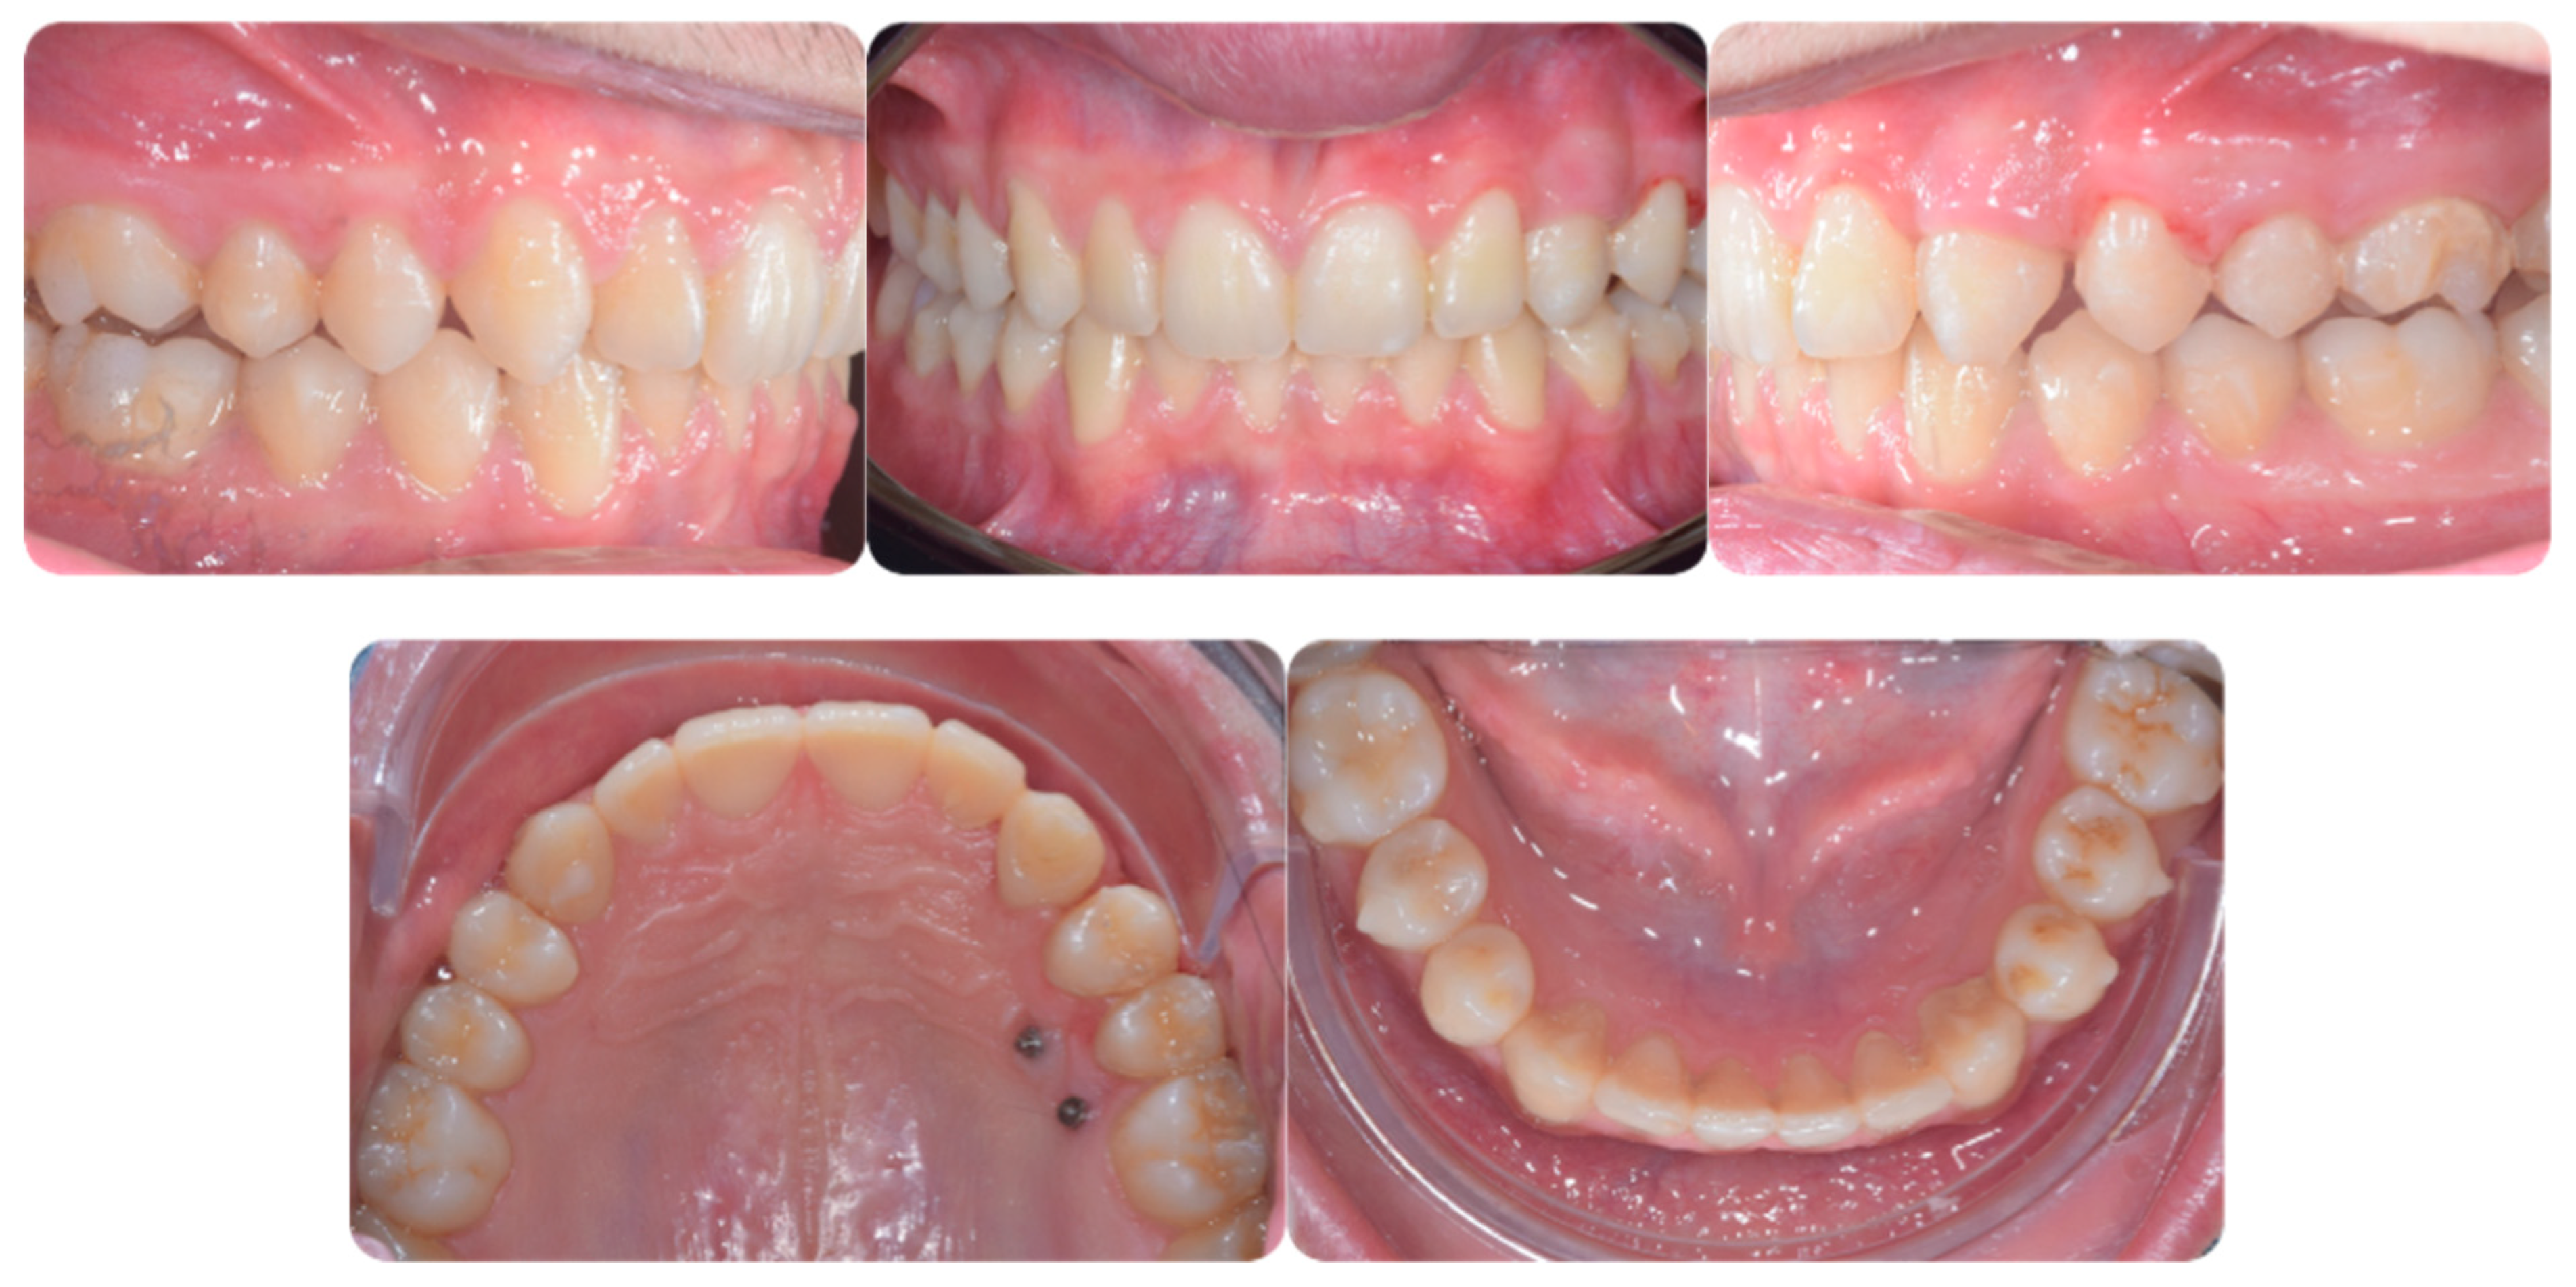

An adult female patient, 43 years old, with Class I occlusion on both sides and with a slight deep bite, light crowding, a persistent deciduous canine no. 63, and a horizontally impacted canine with the crown tip close to the lateral incisors and the tip of the root protruding beyond the buccal bone in the 2.3 area is presented in Figure 9 and Figure 10.

Figure 9.

Class I occlusion on both sides with a slight deep bite, light crowding, a persistent deciduous canine no. 63, and a horizontally impacted canine with the tip of the crown close to the lateral incisors and the tip of the root protruding beyond the buccal bone in the 2.3 area.

Figure 10.

CBCT pictures of the patient. Since the patient was subjected to periodic radiographic control as she was a cancer survivor, the decision was to do a CBCT to receive all the informations useful for the deimpaction treatment and avoid conventional orthodontic X-rays like panoramic and lateral X-rays.